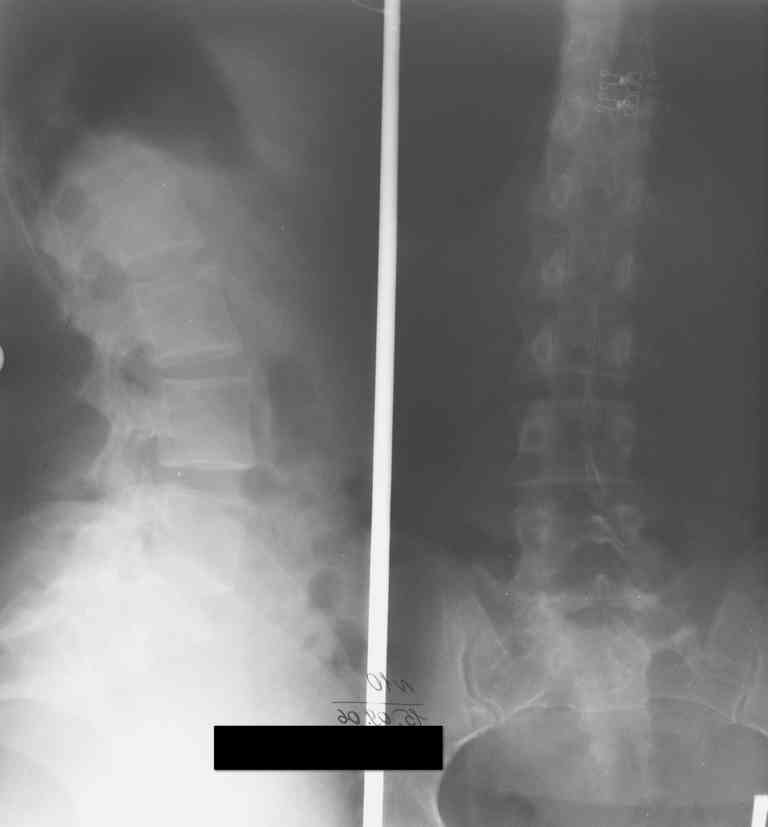

13/03/03 |  13/03/03 |  13/03/03 |  15/09/06 |  15/09/06 |  07/03/07 |  07/03/07 |  19/12/06 | К нам в клинику поступила пациентка 30 лет с диагнозом: Постравматическая ротационная стабильная деформация тазового кольца. Относительное укорочение левой н\конечности на 1 см. Левосторонний компенсаторный сколиоз 2 ст. Болевой синдром. травма автодорожная в январе 2003г. Пассажирка переднего сидения ваз 2109. лечились положением по Волковичу. С марта 2003 года жалуется на боли в тазу, ппояснице усиливающиеся при движении.В настоящее время жалобы на боли в области крестца, КПС больше слева, в пояснично-крестцовом отделе позвоночника. неприятные ощущения, щелчок при выпрямлении правого тазобедренного сустава из положения полного сгибания. боли в тазу появляются при ходьбе ч\з 100 м, так же при вставании из положения сидя, после сидения в течении 2-3 часов. при ходьбе более 100 м появпяется зябкость стоп больше справа. ходит при помощи трости в правой или в левой руке. без трости боли появляются сразу после начала ходьбы. пальпация болезненна в паравертебральных точках средне-грудного и пояснично-крестцового отделов позвоночника, КПС с обеих сторон. Объем движений в тазобедренных суставах полный.правый КПС заблокирован. симптомы натяжения с обеих сторон отрицательны.С 2003г. лечится консервативно, получала ЛФК, массаж, физиолечение - без эффекта. в 2005г. лечилась в санатории с ортопедическим уклоном, получала плавание в минеральной воде, магнитотерапия, массаж, ЛФК. отмечала умеренное улучшение в течении 2 недель.Вопросы:надо ли оперировать, т.е. устранять относительное укорочение левой н\конечности и как?Если не оперировать, то как лечить консервативно?Р-граммы, КТ прилогаются.

Проблема Вашей пациентки находится на границе интересов специальностей ортопедия (вертебралогия) и неврология (нейрохирургия), вероятно, поэтому так мало откликов на ваше обращение. Представленные рентгенограммы не все информативны (особенно спондилограммы от сентября 2006 года). Вероятно, необходимы дополнительные методы исследования к.т. МТГ, ЯМРТ, миелография.

просьбе. досылаю КТ, фуккциональные Р-граммы пояснично-крестцового отдела позвоночника, фото пациентки.

Уважаемый Максим. Снимки от 7.03.07 и есть функциональные, т.е. стоя на правой, и левой ноге.